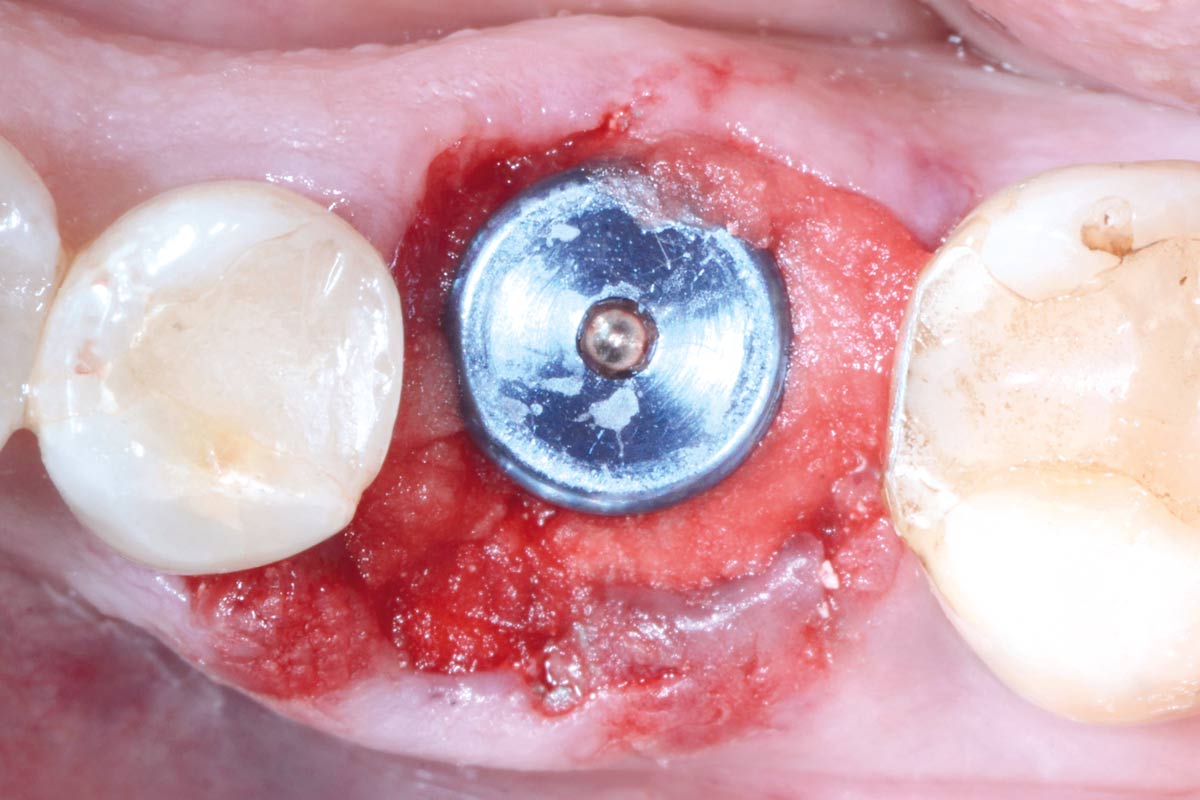

Immediately placed implant covered with permamem®. permamem® passively immobilized by sutures and intentionally left exposed to the oral cavity.